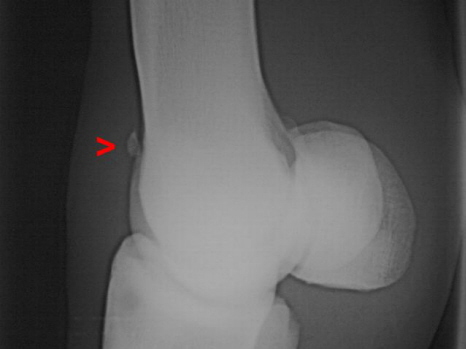

Chip Fesselgelenk